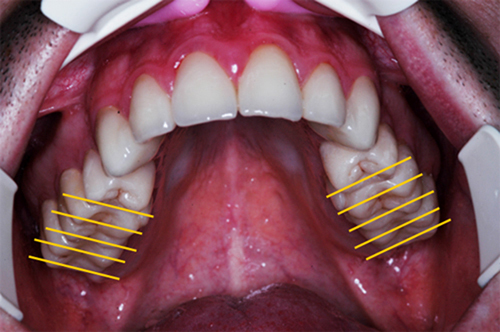

REHABILITACION ORAL MEDIANTE CORONAS DE PORCELANA DE ALTA DENSIDAD Protocolo D.A.T.O. CASO CLINICO: Paciente 24 años, bruxómano, atresia maxilar, referido por ortodoncista para realizar rehabilitación oclusal . Se observa a la inspección la presencia de una hipoplasia adamantina en todos los dientes anteriores, carencia de Guía Anterior , evidentes signos de Facetas Parafuncionales de Desgaste en los posteriores, y una marcada convergencia de los ejes dentarios ápico oclusal, tanto en el maxilar superior como en el inferior, siendo el superior el mas difícil de resolver dado que la inclinación de la Curva de Wilson es inversa a lo que presenta el enfermo. Radiograficamente sin patologías presentes. No presenta movilidades dentarias ni síntomas articulares en las ATM. Debido a la excesiva contractura de su musculatura, se realiza la relajación obviando el uso corriente de las Laminillas de Long, reemplazando el método por un Jig de Lucia el que se deja en boca desde la noche anterior a la cita, advirtiendo al paciente que no debe quitarlo en ningún momento , ya que de hacerlo se repetirían los engramas musculares anómalos que el enfermo presenta. En esas condiciones se toman registros intermaxilares mediante silicona de registros, y se registra el maxilar superior respecto del plano de Frankfort mediante arco facial estático. Se llevan a cabo los encerados correspondientes y se construye en base a ellos el primer juego de provisionales, los que no son cementados debido al perfecto anclaje que presenta. Transcurridos seis meses del uso de provisionales , durante los cuales se ha observado la Oclusión en Relación Céntrica (ORC) inalterable, la ausencia de desgastes patológicos (en las provisorias) y la ausencia de síntomas articulares y musculares, deducimos que el paciente se mantiene en una orto función adecuada, por lo cual comenzamos su rehabilitación definitiva construyendo su Guía Anterior ( determinante primario de la oclusión) en porcelana sobre porcelana de alta densidad.. Observamos los espacios correspondientes en los sectores posteriores y las Disclusiones de los mismos. Los tallados ha sido realizados mediante el concepto de Tallados Gnatológicos, recreados por el Prof. Alvarez Cantoni bajo la denominación de “Preparaciones Racionales”( PREPARACIONES RACIONALES EN PRÓTESIS PARCIAL FIJA. Ed. Hacheace) probando finalmente el trabajo luego de varios días de cementado provisional, y observando la adaptación periférica del borde cavo superficial , su aspecto estético y el importante factor disclusivo : CURVA DE WILSON. y verificando la eficacia lograda mediante una Oclusión Mutuamente Compartida, en la observación de una Disclusión derecha en el Lado de Trabajo y no Trabajo de una disclusión izquierda como así también en la disclusión propulsiva Utilizamos papel de articular de ocho(8) micras para verificar la eficacia de las disclusiones. y de los puntos interoclusales de contacto ANTES DESPUES